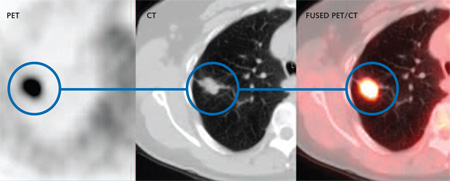

Đây quả là câu hỏi thú vị và rất có giá trị trong bối cảnh nhiều cơ sở y tế, đặc biệt là y tế tư nhân đã lạm dụng nhiều loại phương tiện chẩn đoán cận lâm sàng mau thu hồi vốn đãbỏ ra, tuy nhiên các chẩn đoán hình ảnh PET-CT lại có giá trị của nó. Theo các nhà chuyên môn cho thấy một kỹ thuật chẩn đoán ung thư mới có thể tìm kiếm các vị trí ung thư di căn, phát hiện tổn thương nguyên phát của ung thư, thậm chí phát hiện ung thư ngay khi cơ thể chưa hình thành tổn thương về mặt cấu trúc đã được đưa vào ứng dụng tại nhiều bệnh viện tuyến trung ương. Đó là tổ hợp thiết bị y khoa PET/CT và máy gia tốc Cyclotron. Đây là thiết bị y khoa hạt nhân áp dụng công nghệ kết hợp giữa máy PET và máy CT-scanner. Thiết bị này không chỉ có tác dụng trong lĩnh vực ung bướu mà còn giúp bác sĩ nâng cao chất lượng chẩn đoán và theo dõi nhiều loại bệnh khó trong các lĩnh vực khác như thần kinh, tim mạch. Đối với việc chẩn đoán và điều trị ung thư, việc ghi hình bằng PET/CT có thể giúp phát hiện ung thư giai đoạn sớm ngay sau khi cơ thể chỉ mới có sự thay đổi bệnh lý về chuyển hóa mà chưa hình thành tổn thương về mặt cấu trúc. Thiết bị còn giúp tìm kiếm các vị trí ung thư di căn, vị trí ung thư nguyên phát, giúp các bác sĩ tiên lượng các phương pháp điều trị hiệu quả hơn và đưa ra phác đồ điều trị bệnh lý cho bệnh nhân.

Để chụp PET/CT, bệnh nhân sẽ được tiêm tĩnh mạch một liều thuốc có phóng xạ positron- là một chất dẫn xuất glucose vì các tế bào ung thư sẽ hấp thụ và chuyển hóa nhiều glucose hơn các tế bào khác. Sau khi được tiêm thuốc có phóng xạ, cơ thể sẽ phóng ra các tua gamma và máy PET/CT sẽ tính toán từ các tua gamma này để thu nhập hình ảnh từ các tế bào khác nhau của cơ thể. Nhờ đó, những bất thường về chuyển hóa tại các tế bào sẽ được ghi nhận, ngay trước khi có sự thay đổi về cấu trúc.

Trong khi đó, các phương pháp chẩn đoán hình ảnh khác như chụp cắt lớp vi tính, cộng hưởng từ, siêu âm chỉ phát hiện và đánh giá được các tổn thương khi đã có những thay đổi về cấu trúc giải phẫu ở mức độ đủ lớn và bỏ qua các tổn thương có đường kính dưới 1cm. Mặt khác, ở những bệnh nhân ung thư sau phẫu thuật, xạ trị, hóa trị, các tổn thương có thể biến dạng, thay đổi cấu trúc nên hình ảnh CT/ MRI vẫn có những hạn chế trong việc xác định các tổ chức còn sót tế bào ung thư, không phân biệt được các tế bào xơ hóa với tái phát và di căn. Cũng nhờ khả năng ghi nhận chính xác những bất thường PET/CT không những được dùng trong việc phát hiện sớm ung thư mà còn được dùng để đánh giá các phát triển của ung thư, sự di căn hay phát triển của ung thư tới các cơ quan khác của cơ thể hay sự tái phát của bệnh.

2. Phương pháp chụp PET/CT có thể phát hiện được khoảng 80% các ung thư

Như trên đề cập PET/CT là thiết bị y khoa hạt nhân áp dụng công nghệ kết hợp giữa máy PET và máy CT, có thể phát hiện được khoảng 80% các loại ung thư. Đối với việc chẩn đoán và điều trị ung thư, việc ghi hình bằng PET/CT có thể giúp phát hiện ung thư giai đoạn sớm ngay sau khi cơ thể chỉ mới có sự thay đổi bệnh lý về chuyển hóa mà chưa hình thành tổn thương về mặt cấu trúc. Đặc biệt thiết bị còn giúp tìm kiếm ở các bệnh nhân vị trí ung thư di căn, vị trí ung thư nguyên phát, giúp các bác sĩ tiên lượng và có nững phương pháp điều trị hiệu quả.

Nguyên lý cơ bản của kỹ thuật chụp PET/CT là ghi lại hình ảnh chuyển hóa trong tế bào (ở mức độ phân tử, mức độ tế bào). Sau đó hình ảnh ghi lại bằng máy PET/CT sẽ cho chúng ta thông tin về các thay đổi chuyển hóa của tế bào tổ chức (bằng máy PET), vừa xác định được vị trí chính xác của tổn thương (bằng máy CT). Để chụp PET/CT, bệnh nhân sẽ được tiêm tĩnh mạch một liều thuốc có phóng xạ positron, là một chất dẫn xuất glucose vì các tế bào ung thư sẽ hấp thụ và chuyển hóa nhiều glucose hơn các tế bào khác. Sau khi được tiêm thuốc có phóng xạ, cơ thể sẽ phóng ra các tua gamma và máy PET/CT sẽ tính toán từ các tua gamma này để thu nhập hình ảnh từ các tế bào khác nhau của cơ thể. Nhờ đó, những bất thường về chuyển hóa tại các tế bào sẽ được ghi nhận, ngay trước khi có sự thay đổi về cấu trúc.